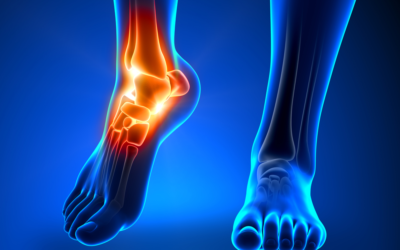

Ask a Foot and Ankle Specialist: How Do I Know If an Ankle Injury Is Serious?

We use our feet and ankles for almost everything, from getting up in the morning to walking to the bus stop. For this reason, ankle injuries can be so frustrating and stressful, even though they are very common and happen to millions of people every year. By visiting...